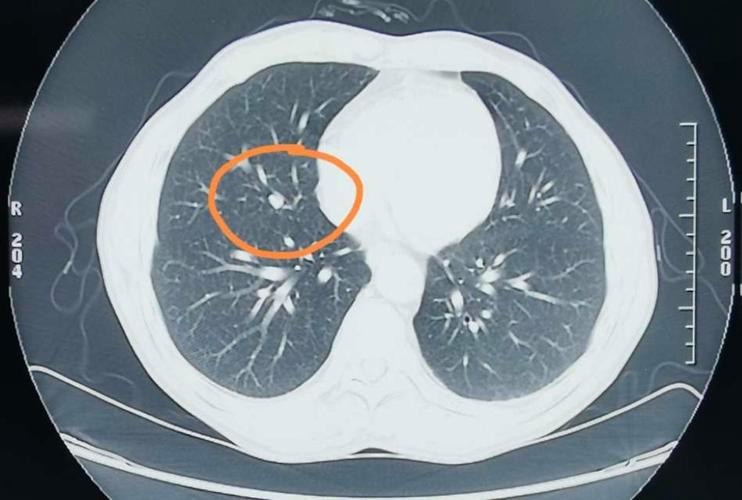

肺结节是一种影像学诊断,指的是肺内出现直径小于3cm的类圆形或不规则形的病灶,在胸部x线和胸部CT上多表现为胸部区域的密度增高,影也可单发也可多发。

根据病灶直径的大小,结节直径一般是在2~3厘米,直径小结节直径是小于等于两厘米微小结节直径小于等于一厘米,而肺结节并不特指于一种疾病,很多疾病也会导致肺部出现结节的问题,从而就会对身体造成伤害。

结节形态: 良性肺结节形态是规则的并且边缘清晰,而恶性肺结节一般形态不规则,边缘模糊。

结节大小: 肺结节小于0.8厘米,更大可能性是良性大于三厘米,更加倾向于恶性。

周围组织受累情况: 肺结节周围淋巴受到牵连,此时肺结节可能会出现恶化的情况。

结节密度: 良性肺结节密度一般都是比较均匀的,并且中心部分存在脂肪密度或者是空气,而恶性结节当中的密度是不均匀的,有时候会存在囊肿或者是坏死的症状。